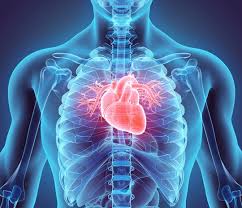

5. 심장을 감싸는 구조

- 심막(pericardium): 이중벽 구조로 심장을 둘러싸며, 척추, 횡격막, 대혈관에 연결돼 안전하게 위치합니다 :contentReference[oaicite:15]{index=15}.

- 내막(endocardium), 중간 근육층(myocardium), 외막(epicardium)으로 구성돼 있습니다 :contentReference[oaicite:16]{index=16}.

6. 심장의 기능과 위치 연관성

- 흉골 바로 뒤·좌측에 위치해 늑골이 물리적 보호를 제공하지만, 흉부 충격 시 손상 위험도 있습니다.

- 척추·횡격막과 공조하며 심장은 지속적으로 왕복 펌프 작용을 수행합니다 :contentReference[oaicite:17]{index=17}.

- 심장이 폐 사이에 위치해 폐와 연결된 혈관 구조가 복잡하게 얽혀 있으며, 심폐 기능이 조화롭게 이루어집니다 :contentReference[oaicite:18]{index=18}.